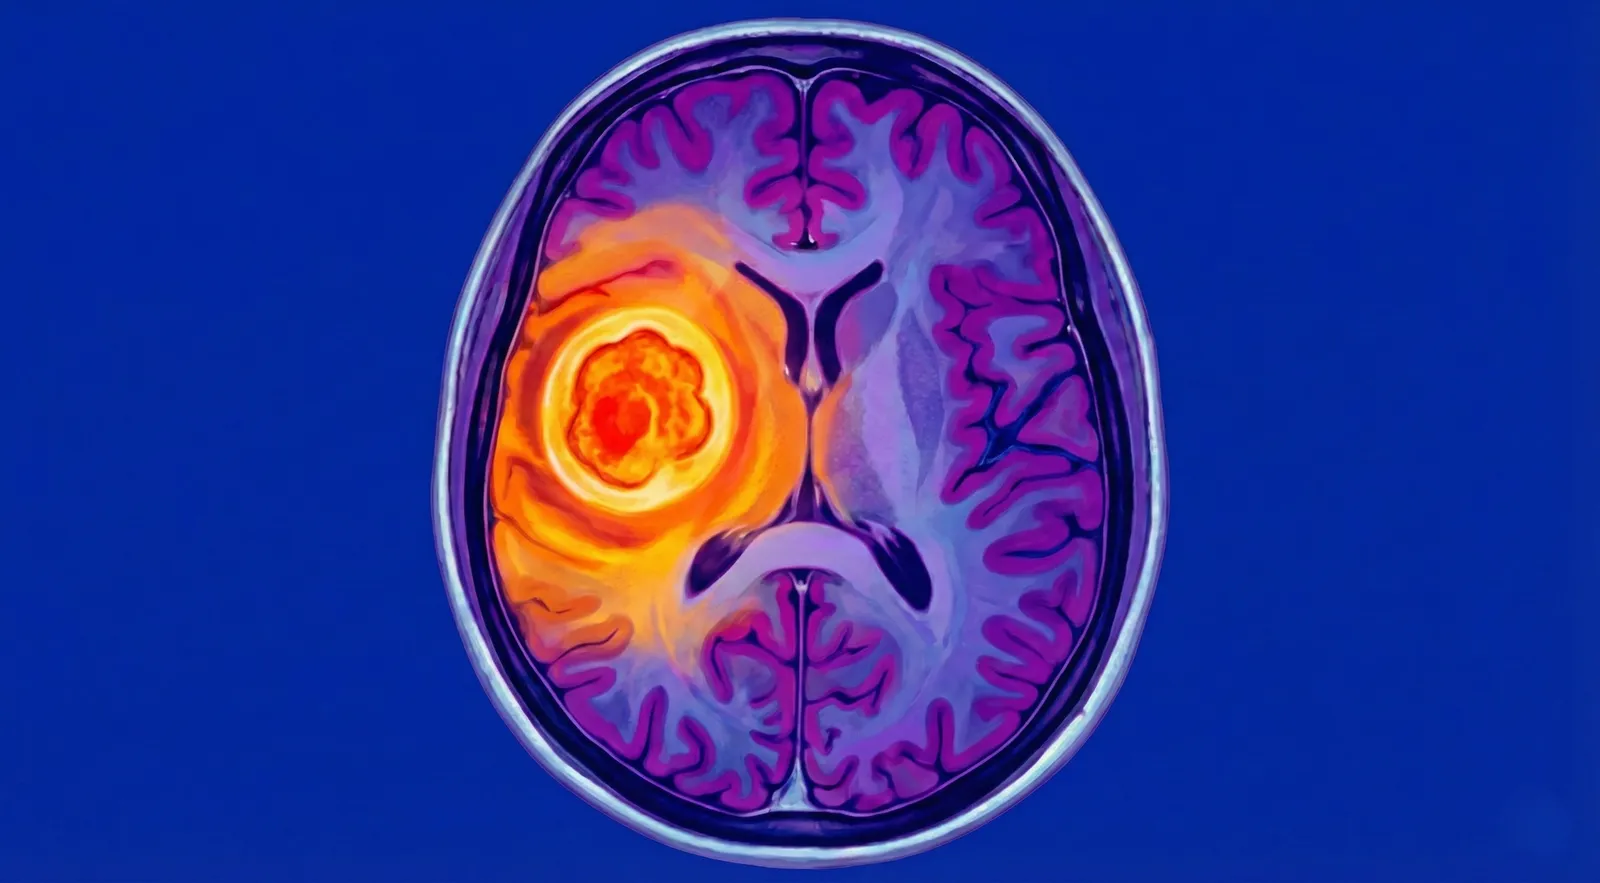

🧠 Abscesso Cerebral

> "Uma bolsa de pus dentro do cérebro — emergência que precisa de antibióticos e, muitas vezes, cirurgia imediata"

Uma bolsa (coleção) de pus — resultado de bactérias, fungos ou parasitas — que se formou dentro do tecido cerebral. Funciona como um "balão" ocupando espaço, comprimindo o cérebo e aumentando a pressão dentro da cabeça.